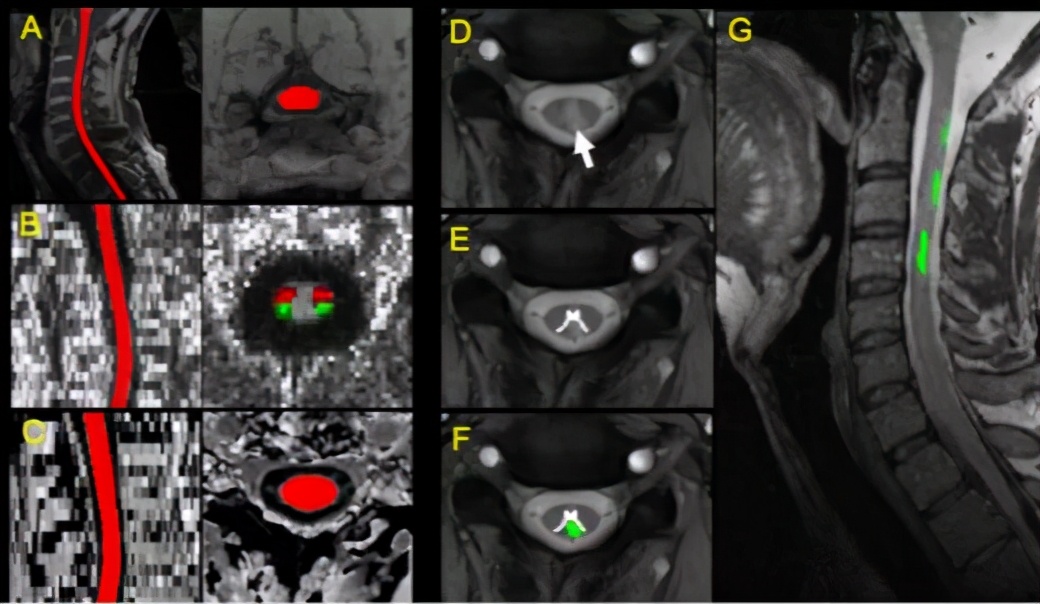

该研究是单中心临床磁共振成像研究,运用多模态定量脊髓磁共振成像(quantitative spinal cord MRI)技术,招募了多发性硬化症患者、MOG-Ab疾病患者、AQP4-Ab疾病患者和健康志愿者共80人,获取其颈部等区域脊髓的截面积、病灶分布、纤维束各向异性分数和磁转化率等多项定量指标(图1),用于区分三种中枢神经系统脱髓鞘疾病,并评估其与残疾指数和病理性疼痛等临床指标的关联性。

图1 (A)脊髓结构分割示意,(B)各向异性分数(FA)图、脊髓丘脑束(红色)和皮层脊髓束(绿色),(C)磁转化图像分割,(D)T2* 轴位图,显示灰质和病灶,(E)灰质分割,(F)病灶分割,(G)病灶配准到T2结构像。